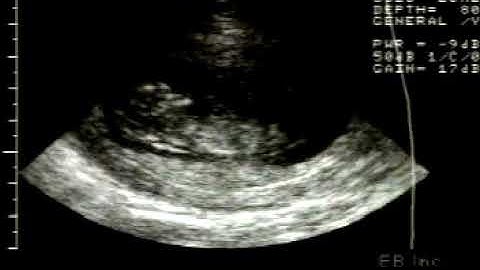

CVS from Posteriorly located Placentae: Methods to overcome difficulties | OBG CUHK